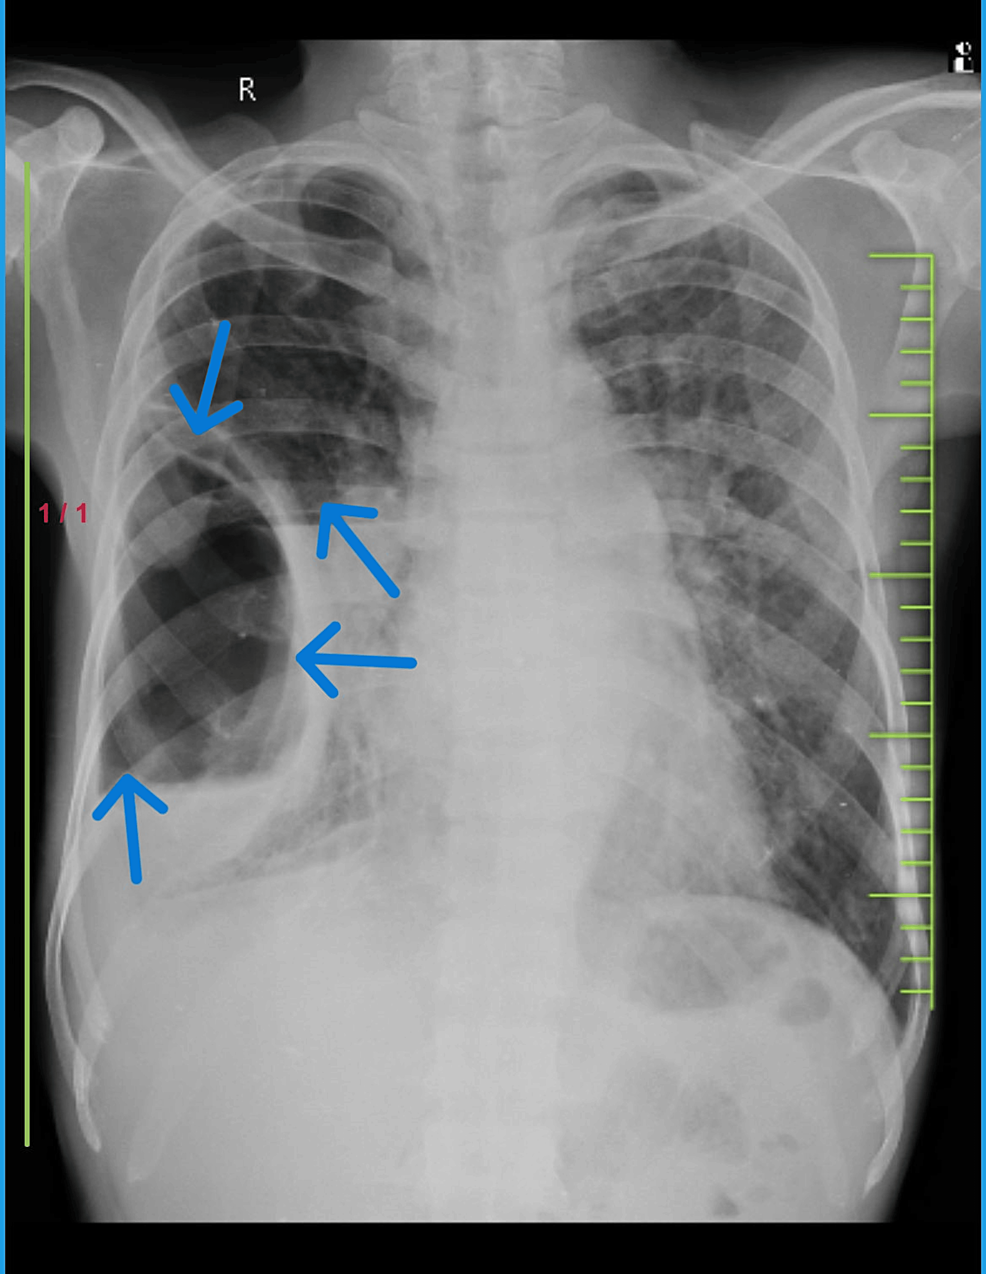

- Chest X-ray: A standard chest X-ray can often reveal the presence of large bullae as lucent (dark) areas within the lung fields, often with flattened diaphragms and hyperinflated lungs. However, smaller bullae or those obscured by other lung structures may not be visible.